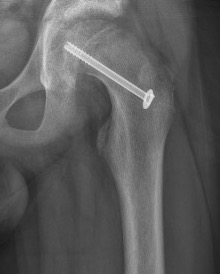

Fixation failure

Cam FAI

Mechanism

Epiphysis heals in a posterior and inferior position with moderate - severe slips

Abnormal contact of relatively anterior neck on the acetabulum